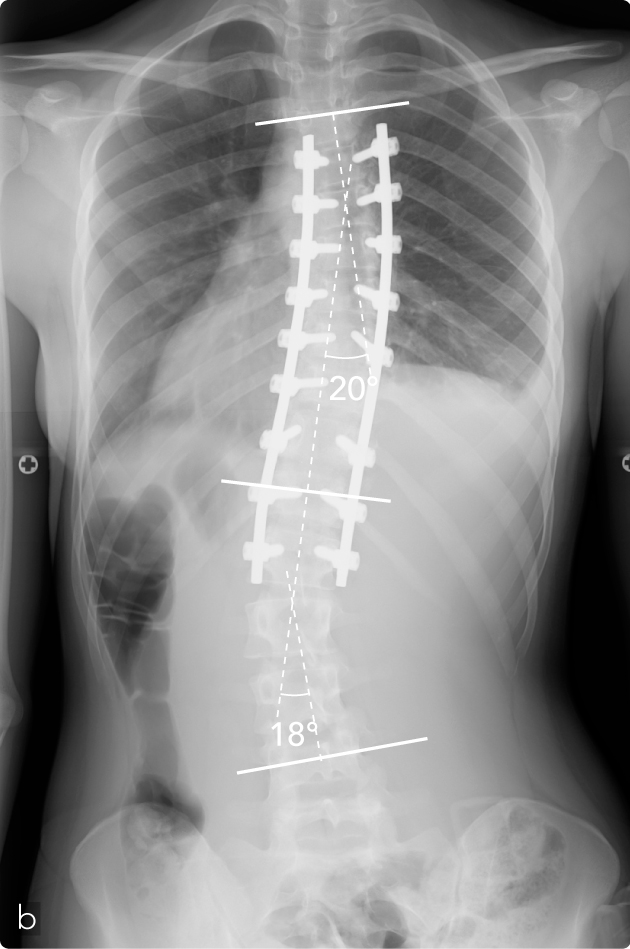

Femmina, 15 anni, scoliosi idiopatica. All'esame ispettivo si apprezza asimmetria dei fianchi, lo sbilanciamento delle spalle rispetto al bacino, la presenza del gibbo dorsale destro alla flessione anteriore del tronco (a). La radiografia mostra scoliosi toracica destra con compenso non strutturato lombare. Operata di artrodesi breve posteriore strumentata (b) con buon risultato estetico e funzionale. Si apprezza al controllo evolutivo buon bilanciamento della colonna vertebrale. Riduzione della deformità toracica da 53° a 20° secondo Cobb e della lombare da 37° a 18° secondo Cobb.